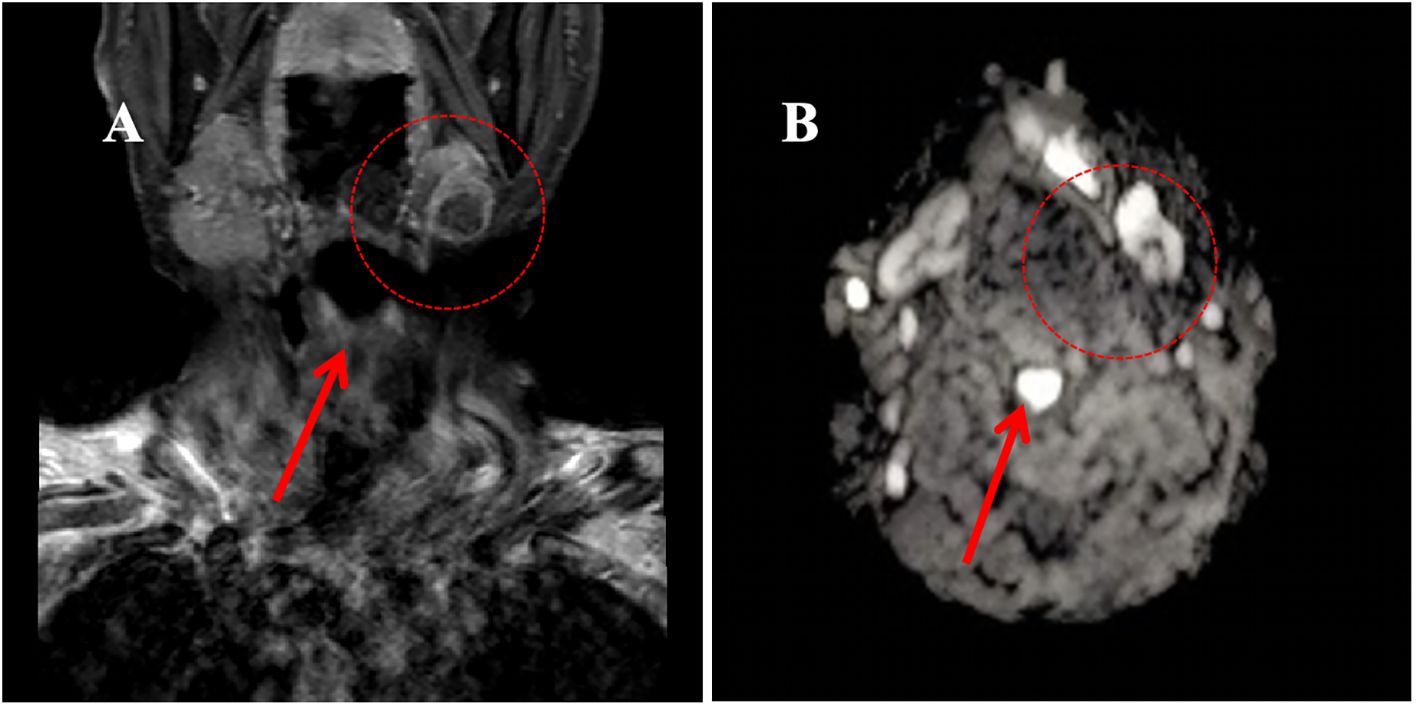

Initial diagnostic imaging included magnetic resonance imaging (MRI) of the head and neck, which identified a 1.5×1.3×1.1 cm calcified lesion within the left submandibular gland (Figure 1). Subsequent contrast-enhanced ultrasonography revealed a heterogeneous hypoechoic nodule with prominent internal vascularity in the left submandibular gland. Fine-needle aspiration biopsy (FNAB) confirmed the presence of infiltrating atypical glandular tissue, suggestive of submandibular gland malignancy.

Figure 2. Magnetic Resonance Imaging (MRI) of the neck region in June 2020. (A) T1-weighted image showing a hypointense lesion in the left submandibular gland (approximately 1.5×1.3×1.1 cm); (B) Diffusion-weighted image demonstrating a hyperintense signal in the left submandibular gland.